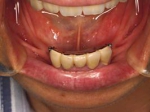

インプラント義歯 ミニインプラント症例

術前術前主訴-総入れ歯の安定が悪い 即時加重可能のミニインプラント使用した。 術前レントゲン術前レントゲン術前レントゲン CT撮影から3次元骨モデルを作成CT撮影から3次元骨モデルを作成CT撮影から3次元骨モデルを作成し埋入位置の確認 フィクスチャーを浸潤麻酔下で埋入フィクスチャーを浸潤麻酔下で埋入。歯茎を切らないので患者さんも非常に楽

4本埋入終了4本埋入終了4本埋入終了(このシステムは4本が絶対条件) 義歯の調整義歯の調整当日に義歯の調整に取りかかる。裏側より義歯をくりぬき維持部のカバー(ハウジング)を義歯の内面に埋め込む step1 義歯の調整義歯の調整当日に義歯の調整に取りかかる。裏側より義歯をくりぬき維持部のカバー(ハウジング)を義歯の内面に埋め込む step2 義歯の調整当日に義歯の調整に取りかかる。裏側より義歯をくりぬき維持部のカバー(ハウジング)を義歯の内面に埋め込む step3

義歯の調整義歯の調整当日に義歯の調整に取りかかる。裏側より義歯をくりぬき維持部のカバー(ハウジング)を義歯の内面に埋め込む step4 義歯の調整義歯の調整当日に義歯の調整に取りかかる。裏側より義歯をくりぬき維持部のカバー(ハウジング)を義歯の内面に埋め込む step5 義歯の裏側義歯の裏側義歯の裏側 装着後しっかり噛める様になる